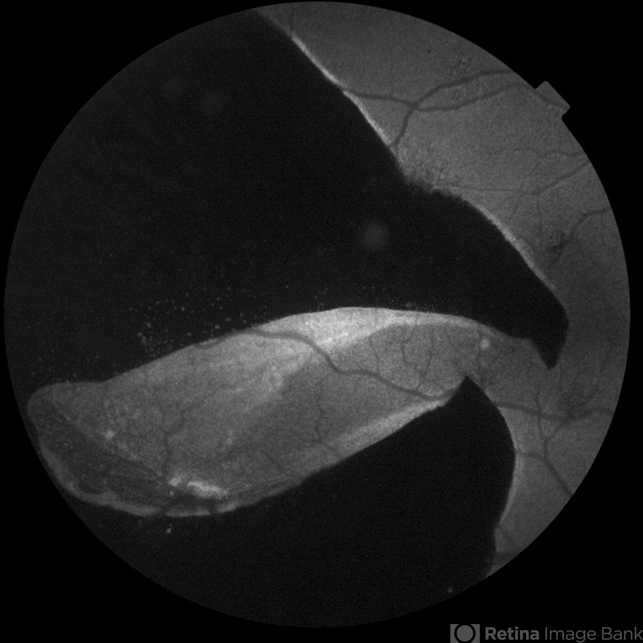

- RPE-rip

- Autofluorescence of a 50 year-old patient with spontaneous giant RPE rip.